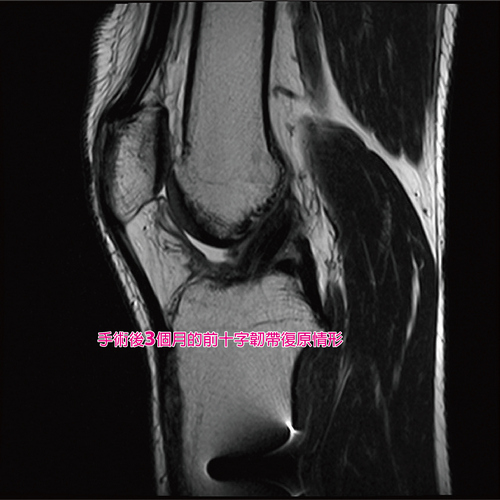

病人手術前前十字韌帶與術後三個月的磁振造影檢查(MRI) 影像,明顯看出復原情形。

病人手術後三個月的前十字韌帶復原情形。